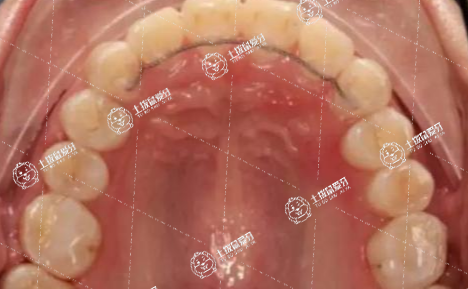

兒童牙齒擁擠早期可以通過(guò)改變不良習(xí)慣、佩戴活動(dòng)矯治器矯正等進(jìn)行干預(yù)。

1.改變不良習(xí)慣:兒童吮手指、咬物等是造成牙齒錯(cuò)位畸形常見(jiàn)原因。通過(guò)干預(yù)、破除吮手指、咬物等不良習(xí)慣可以避免牙齒擁擠加深。

2.佩戴活動(dòng)矯治器矯正:頜骨發(fā)育不足、乳牙滯留或缺失是造成牙齒錯(cuò)位畸形的主要原因??梢酝ㄟ^(guò)佩戴帶有舌簧、弓簧及雙曲唇弓的上下活動(dòng)矯治器矯正排齊前牙,恢復(fù)正常咬合關(guān)系。

兒童牙早期可以通過(guò)佩戴活動(dòng)矯治器、佩戴固定矯正器、拔牙矯正等方法進(jìn)行牙齒矯正。

1.佩戴活動(dòng)矯治器:兒童牙齒不齊早期可以佩戴活動(dòng)矯治器,利用患兒頜面部生長(zhǎng)發(fā)育的潛力,對(duì)牙齒位置異常進(jìn)行相應(yīng)的調(diào)整。

2.佩戴固定矯正器:在每個(gè)牙面上粘貼托槽,固定其上的弓絲,對(duì)牙齒進(jìn)行移動(dòng)或位移控制,從而重新排列牙齒。一般需要1-2年的時(shí)間。

3.拔牙矯正:如牙列擁擠嚴(yán)重,可以采取拔牙的方式進(jìn)行矯正,一般拔除前磨牙,將牙齒向內(nèi)收攏關(guān)閉間隙,使牙齒排列整齊,從而提高面部美觀。